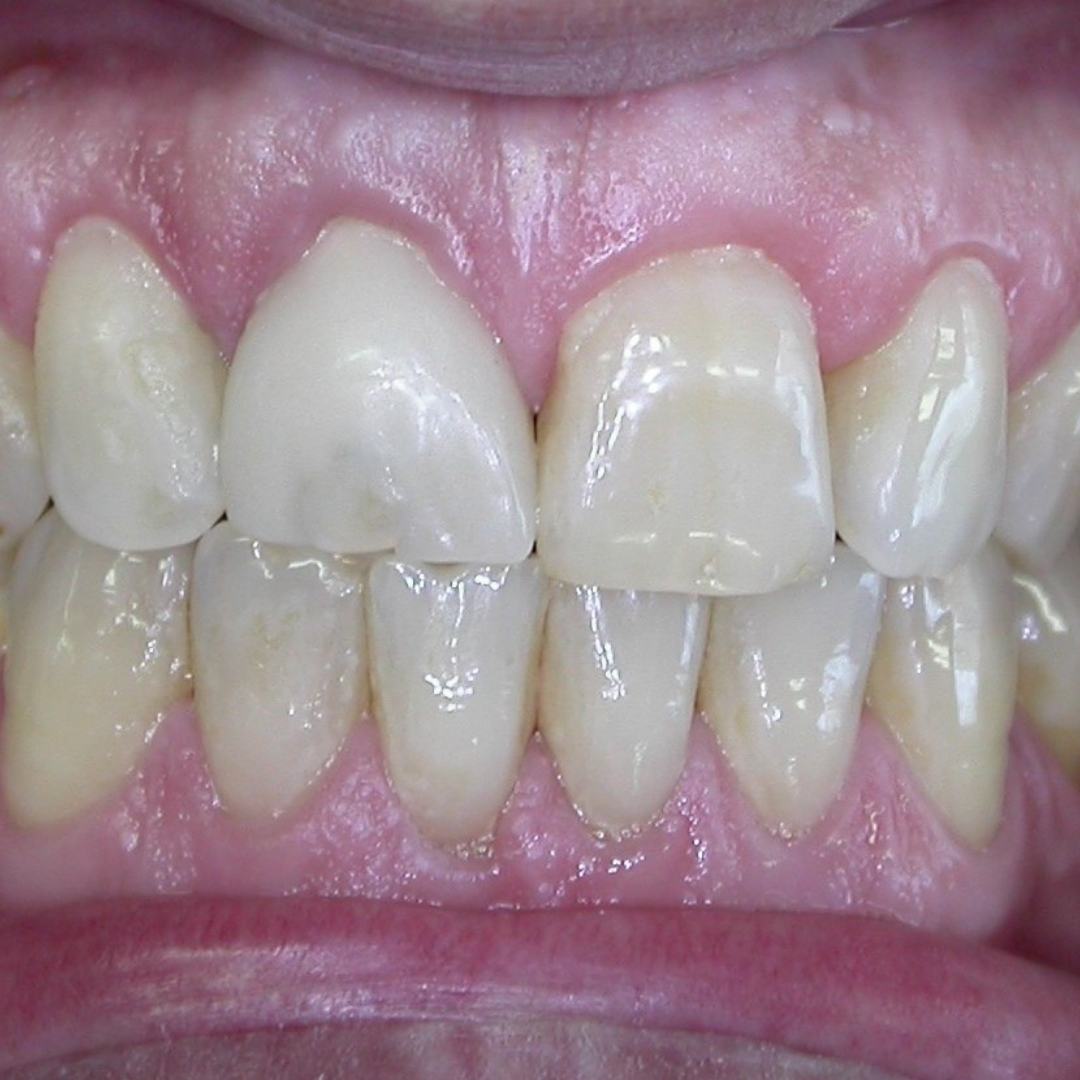

Los implantes dentales no solo restauran tu sonrisa, sino que también preservan la estructura de tus dientes y mandíbula. Al ser colocados de manera quirúrgica en el hueso, funcionan como raíces artificiales, lo que proporciona una base sólida para una prótesis dental que se ve y funciona como un diente natural. Los implantes son una opción duradera y segura, además de ser altamente estéticos, ya que se integran perfectamente con el resto de tus dientes.